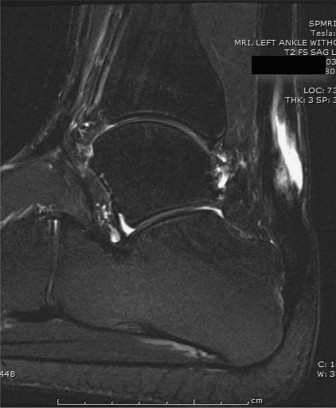

A 53-year-old man presents to your office 2 months after a motor vehicle accident. He reports that he had to …